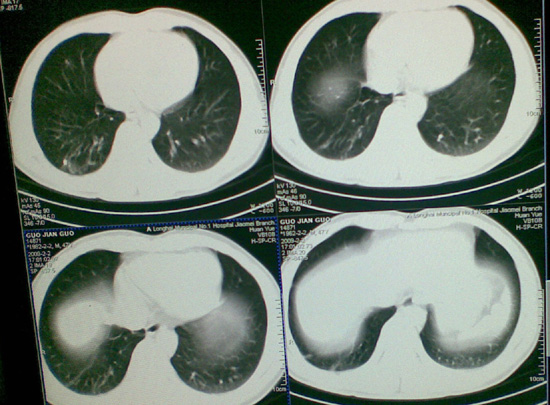

像肺结核钙化吗,不曾见过的影像,请大家帮忙看一下

陈旧性肺结核,钙化。

右肺结核(以纤维增殖、钙化病灶为主)。